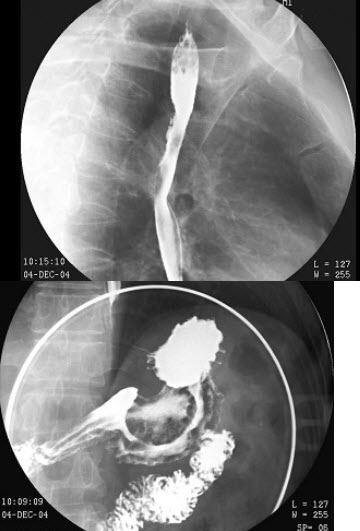

6、单项选择题

男,两月。表现排便困难、便秘、腹胀,经常哭闹。如图所示,最可能的诊断为()

B.膜部

14、单项选择题

男,70岁,进行性吞咽困难半年,结合图像,最可能的诊断为()

C.三尖瓣闭锁

男,55岁,上腹饱胀不适2月,结合图像,最可能的诊断是()

A.正常表现